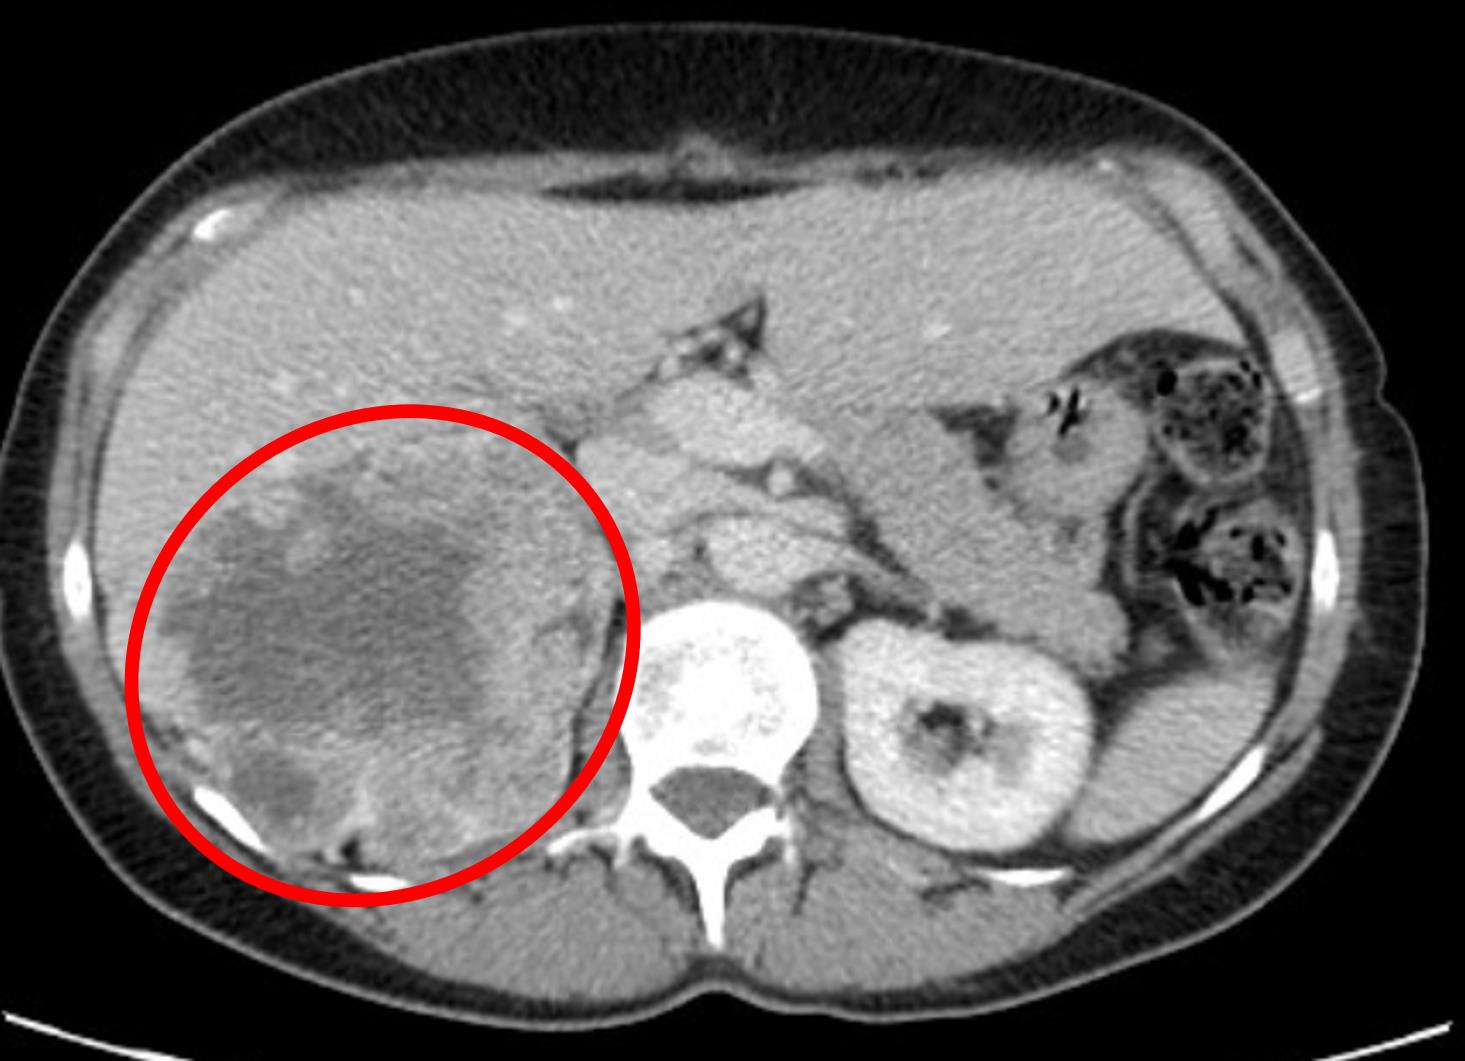

A 66-year-old man presents to his primary care physician with a 2 day history of red colored urine. He first noticed the symptom after returning home from a cruise vacation. He was surprised by the color change because he had not noticed any urgency or pain with urination. He denies fever, chills, or other symptoms. His medical history includes hypertension, hyperlipidemia, chronic obstructive pulmonary disease, and diabetes. His medications include amlodipine, atorvastatin, tiotropium, and metformin. He currently smokes 1 pack of cigarettes per day and has a 30 pack-year smoking history. His temperature is 98.7°F (37°C), blood pressure is 136/88 mmHg, pulse is 80/minute, and respirations are 16/minute. Physical exam reveals no costovertebral angle tenderness or palpable abdominal masses. A CT scan is obtained and the results are shown in Figure A. Which of the following additional findings is most likely to be observed?

Figure/Illustration A is a CT scan of the abdomen demonstrating a large heterogeneous mass in the retroperitoneum (red circle). This finding is consistent with a diagnosis of renal cell carcinoma.

The finding of hematuria in a smoker with a heterogeneous, hypervascular renal mass is suggestive of renal cell carcinoma (RCC). The most common paraneoplastic syndrome in RCC is hypercalcemia of malignancy.